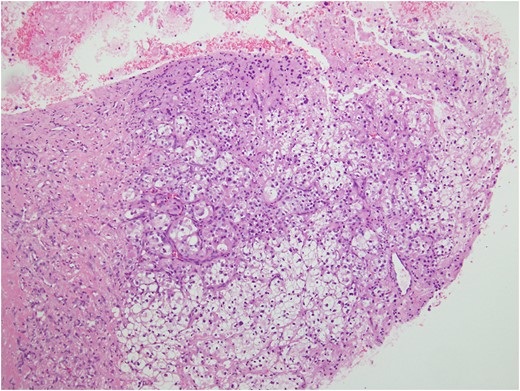

Histologic sections of the mass show distinct variably sized and shaped collections of uniform polygonal tumor cells, separated by fibrovascular septa and delicate capillary-sized vascular channels lined by flattened endothelium at low magnification (Fig. 5). Within the tumor nests, there is loss of cellular cohesion and necrosis of the centrally located cells in the nests results in the pseudo-alveolar pattern (Fig. 6). Vascular invasion is also present (Fig. 7). The individual tumor cells have distinct cell borders and abundant eosinophilic to clear, somewhat granular cytoplasm surrounding a central nucleus with variably sized nucleolus. Nuclear atypia is rarely seen. Mitotic figures are uncommon. The cells contain rhomboid or rod-shaped crystalline inclusions that are faintly apparent on routine histology and are better demonstrated with periodic acid-Schiff stain after diastase digestion (Fig. 8).

Tumor cells are arranged in organoid or nesting pattern. The nests are vary in size and shape and are separated by delicate thin fibrous septa containing vascular channels.